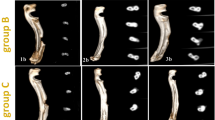

Histopathological examination

Skin sections obtained from the untreated infected rabbits showed extensive histopathological alterations in the epidermal and dermal layers. There were severe epidermal hyperplasia, acanthosis, parakeratosis, and hyperkeratosis along with extensive spongiosis (Fig. 5a). An enormous number of mites and/or burrows were seen in most sections (Fig. 5b). Dermis showed extensive congestion and inflammatory cells infiltration (Fig. 5c). The main inflammatory cells observed are eosinophils, plasma cells and lymphocytes mixed with other cells including neutrophils and macrophages (Fig. 5d). Most of the hair follicles showed folliculitis and converted into small sacs filled with inflammatory cells. There were moderate improvements in the epidermal and dermal lesions of both nanoparticle-treated groups. AgNPs treatment groups displayed moderate to a marked improvement in skin lesions in all treated cases. Some cases showed mild epidermal hyperplasia and hyperkeratosis along with moderate mixed inflammatory cells infiltration within the dermis (Fig. 5e). Other cases showed normal epidermal histology with the proliferation of fibroblast and angioblast in the dermal layer forming organized tissue (Fig. 5f,g). Otherwise, the GNPs receiving group showed the normal histological structure of both epidermis and dermis except for mild dermal edema and lymphocytic exocytosis (Fig. 5h).

Photomicrograph of skin sections stained with H&E that represented diverse groups. (a–d) untreated infected rabbit demonstrated epidermal hyperplasia (red stars), numerous mites/burrows (black triangles), spongiosis (blue triangles), vacuolar degeneration (black arrows), inflammatory cells infiltration (Black stars), and dermal edema (blue stars). (e–g) AgNPs treated group demonstrated mild hyperkeratosis (red triangle), epidermal hyperplasia (red stars), moderate dermal inflammatory cells infiltration (Black stars), and dermal organized tissue formation (red arrows). (h) GNPs treated group demonstrated normal epidermal layer and moderate dermal edema (blue stars).

The outcomes of the quantitative grading were outlined in Table 4. In the epidermis, there was a marked decline in the number of mites/burrows, epidermal layers, exocytic cysts, spongiotic and necrotic cells in both NPs treated groups in contrast to the untreated group but the best improvement was recorded in the GNPs group in comparison with AgNPs group. Regarding the dermal lesion grading, a notable decline in the total number of heterophiles, eosinophils, plasma cells and lymphocytes was recorded in both NPs treated groups along with a mild increase in mast cell counts in contrast to the untreated group.